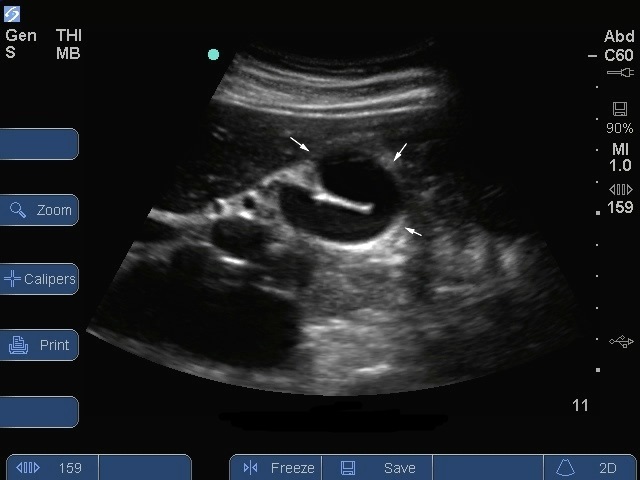

S Series : Vue longitudinale de la vésicule biliaire Vue du bonnet phrygien